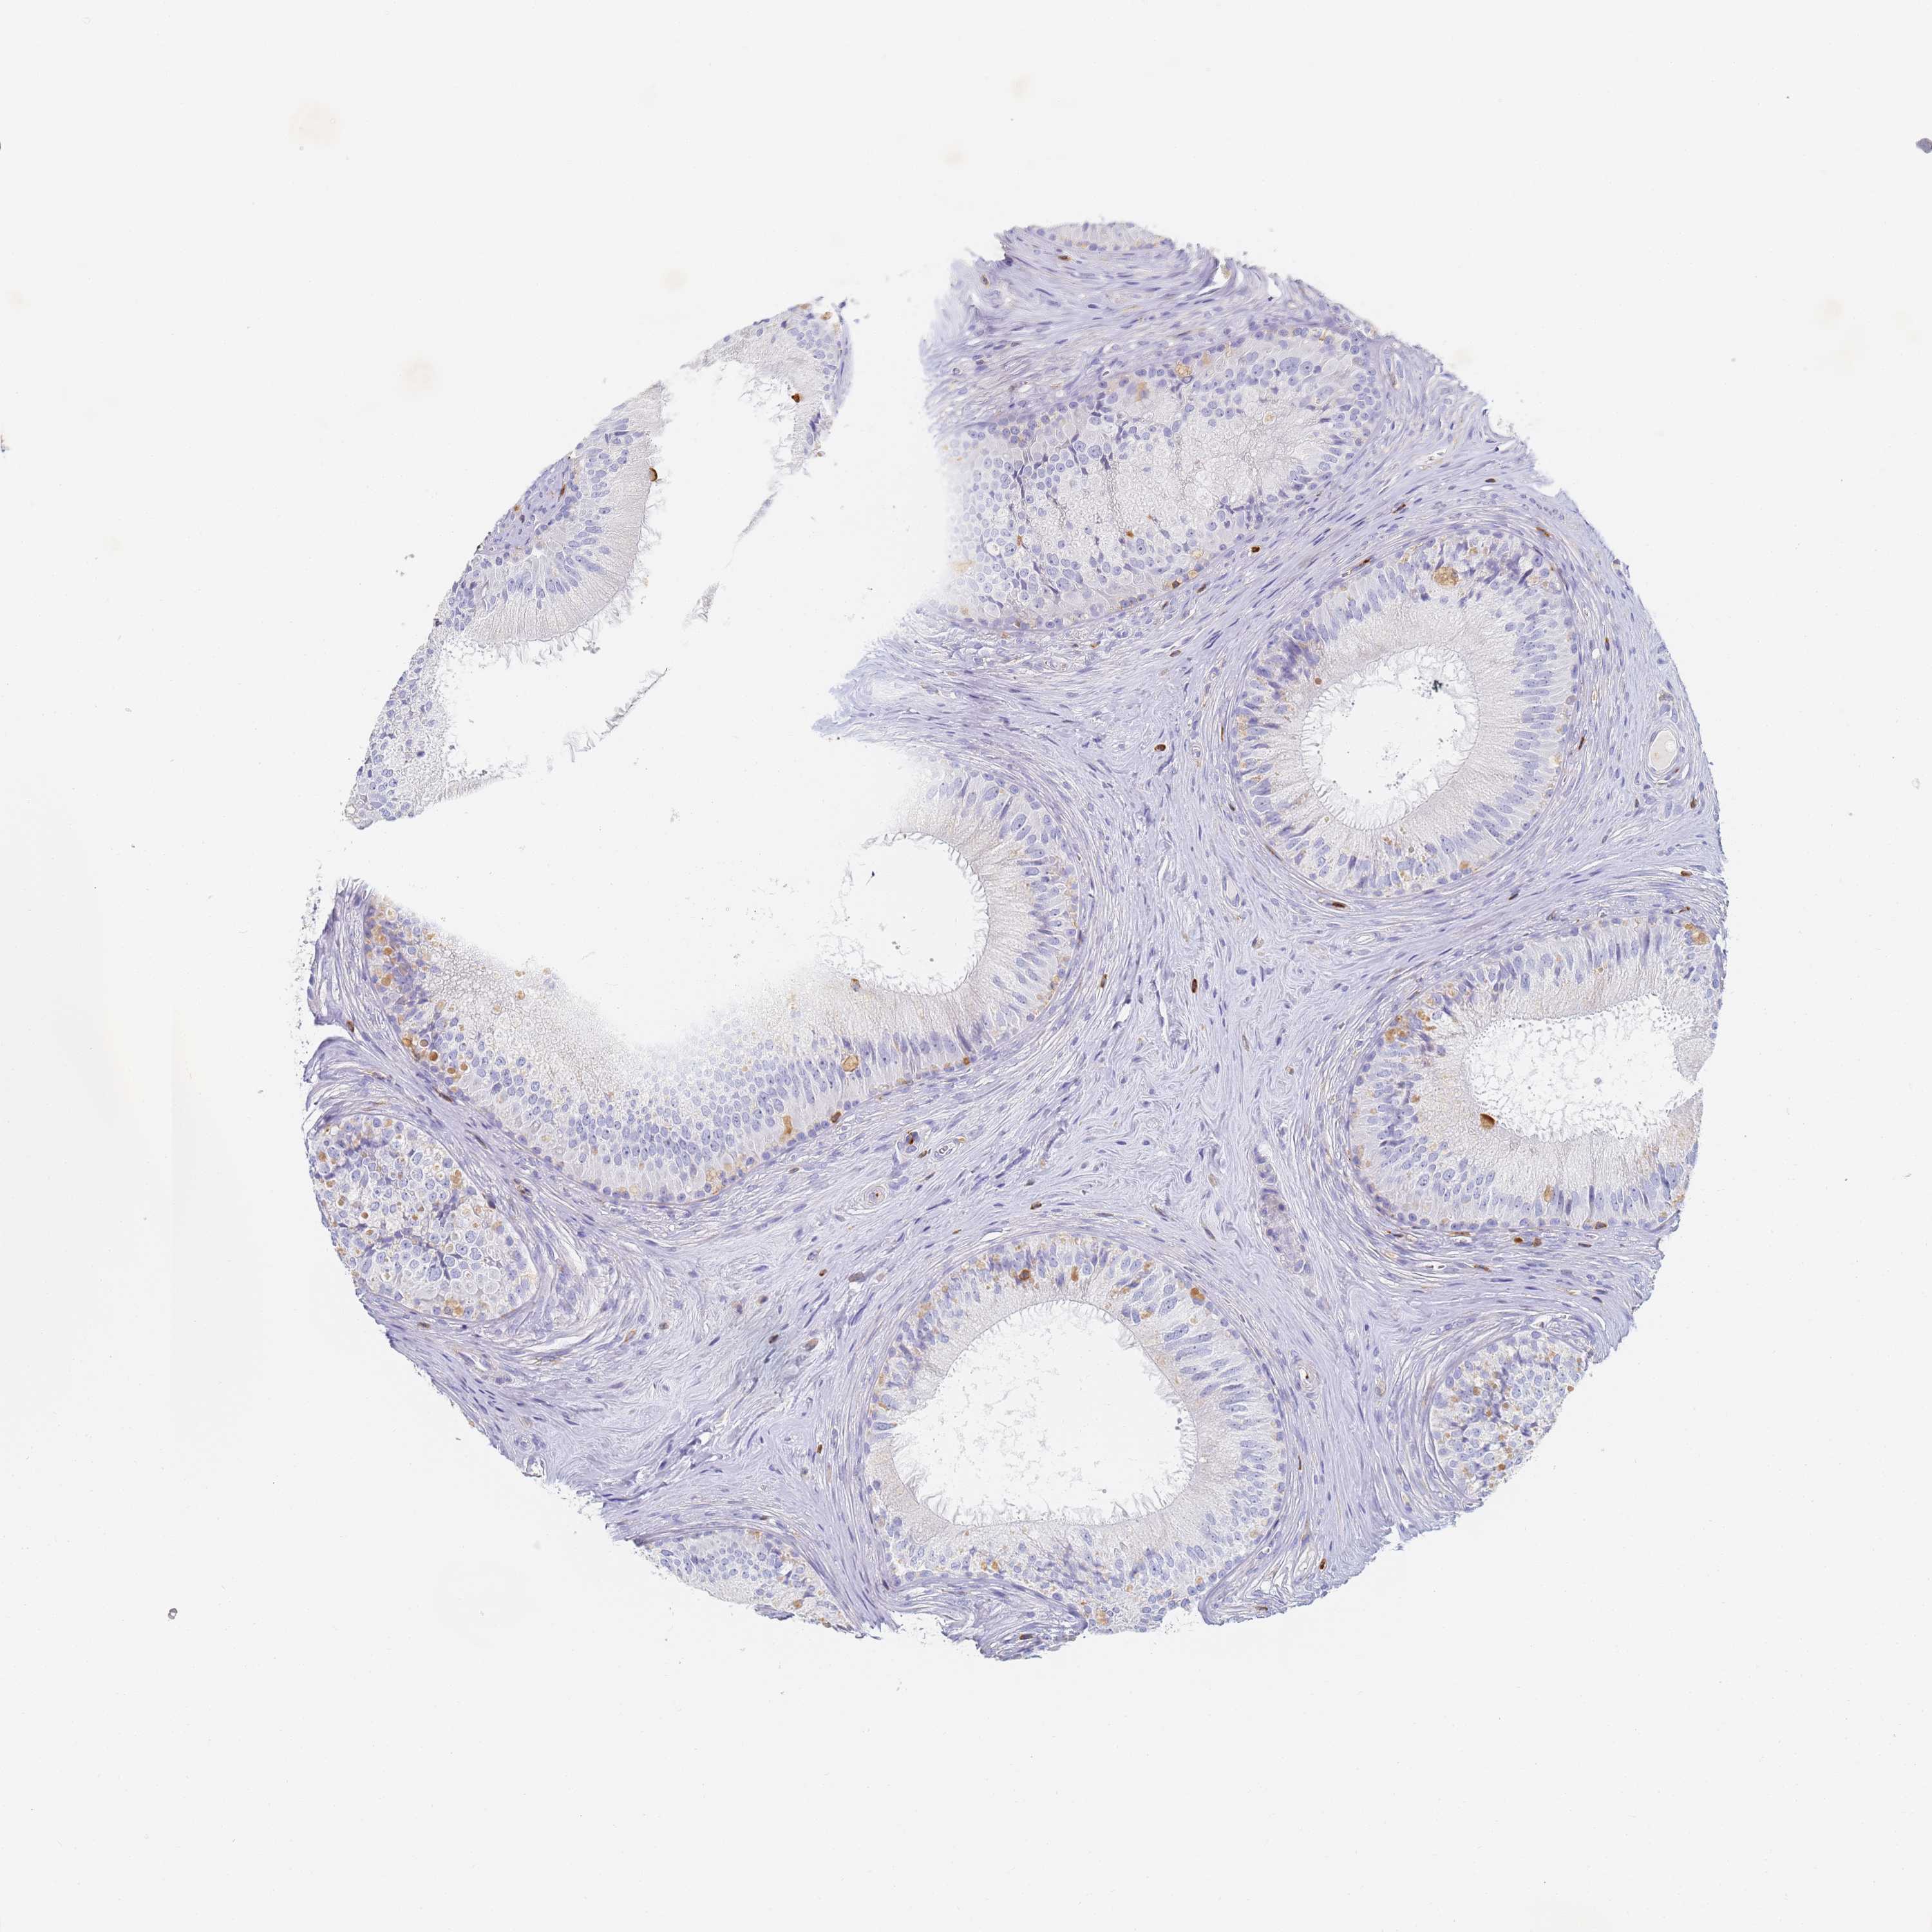

BIN2